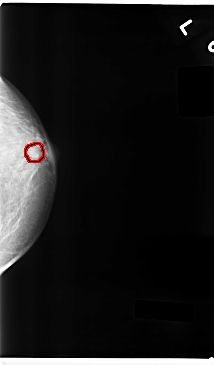

C_0237_1.LEFT_MLO

C_0237_1.LEFT_CC

LEFT_MLO LINES 4752 PIXELS_PER_LINE 2552 BITS_PER_PIXEL 12 RESOLUTION 50 OVERLAY

FILE: C_0237_1.LEFT_MLO.OVERLAY

TOTAL_ABNORMALITIES 1

ABNORMALITY 1

LESION_TYPE MASS SHAPE OVAL MARGINS CIRCUMSCRIBED

ASSESSMENT 4

SUBTLETY 4

PATHOLOGY BENIGN

TOTAL_OUTLINES 1

FILE: C_0237_1.LEFT_CC.OVERLAY

LESION_TYPE MASS SHAPE ROUND MARGINS CIRCUMSCRIBED